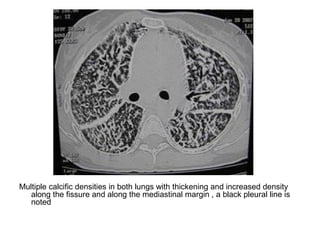

Multiple calcific densities in both lungs with thickening and increased density

along the fissure and along the mediastinal margin , a black pleural line is

noted